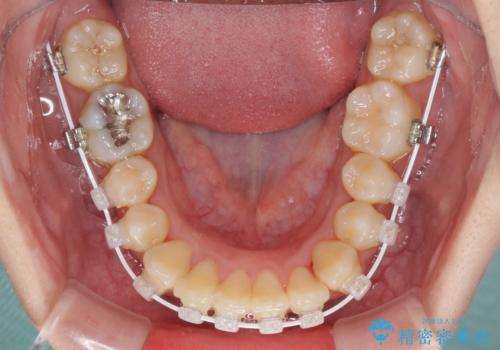

- 審美装置

- 1年3ヶ月

- 10-30回

マウスピースによる矯正治療も提案しましたが、ご自身でのマウスピースの管理の面倒くささと、なるべく早く治療を終えたいとのことで、ワイヤー矯正を選択されました。